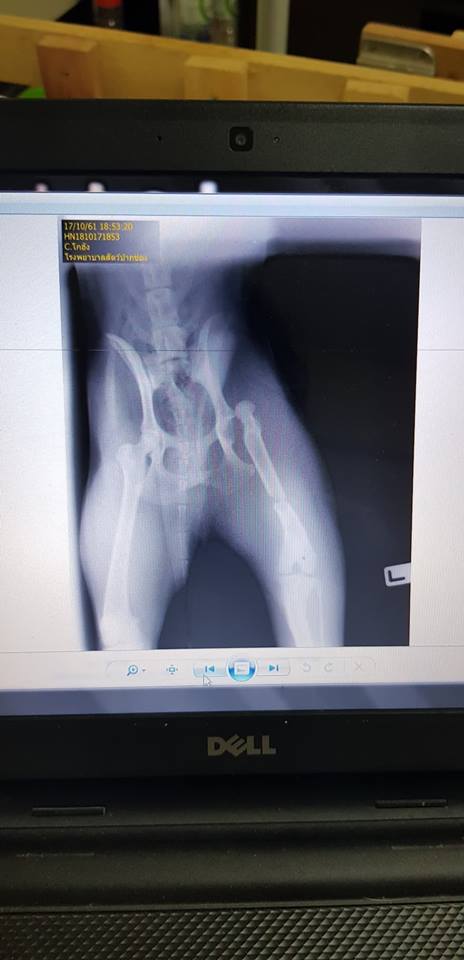

น้องเดินสามขา ท่าทางจะเจ็บมาก เลยรีบพาไปเอ็กซ์เรย์ ปรากฎว่ากระดูกขาหลังหัก กับ สะโพกหลุด ฮืออ

[Spoil] คลิกเพื่อดูข้อความที่ซ่อนไว้แปะรูปเอ็กซ์เรย์ขาน้องค่ะ T^T